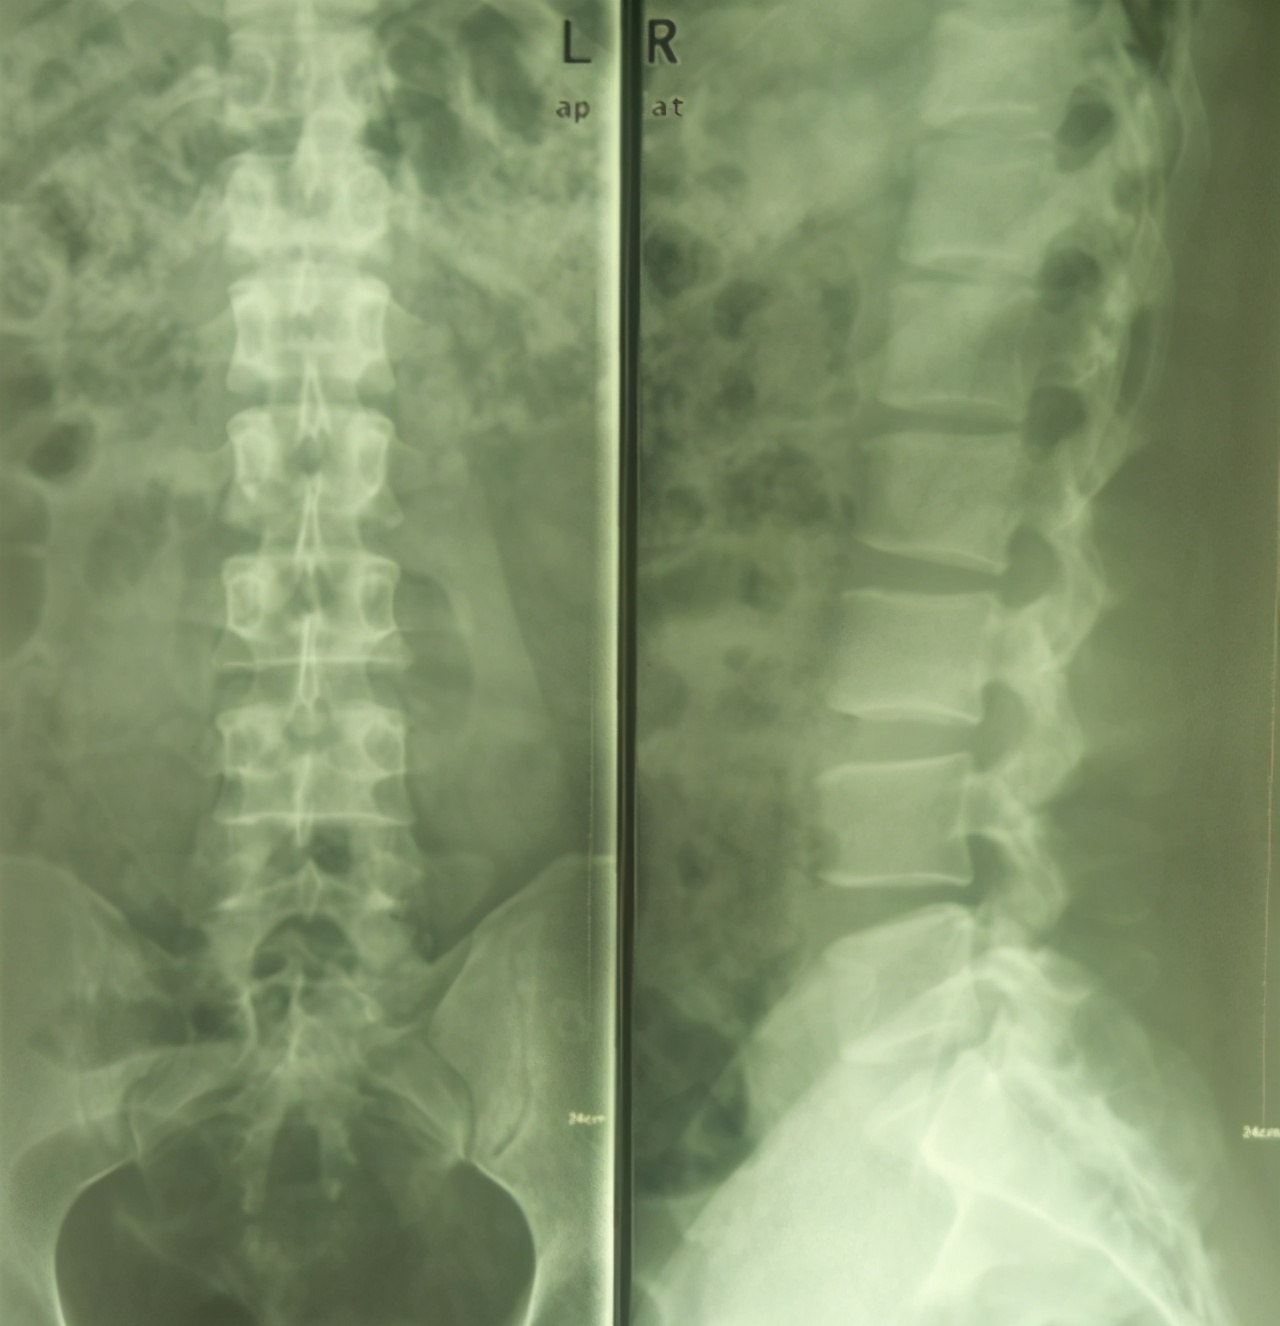

做了放射线,没什么明显的异常。